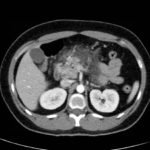

Computed tomography of the abdomen and pelvis with contrast show edema of the pancreas (red outline) and duodenum (yellow arrow) with peripancreatic inflammation, fluid and fat stranding (blue highlight). The distal pancreatic tail was noted to appear normal (green arrow). There was no organized drainable fluid collection, and no parenchymal hypo-enhancement. These findings are consistent with moderate severity acute interstitial pancreatitis.